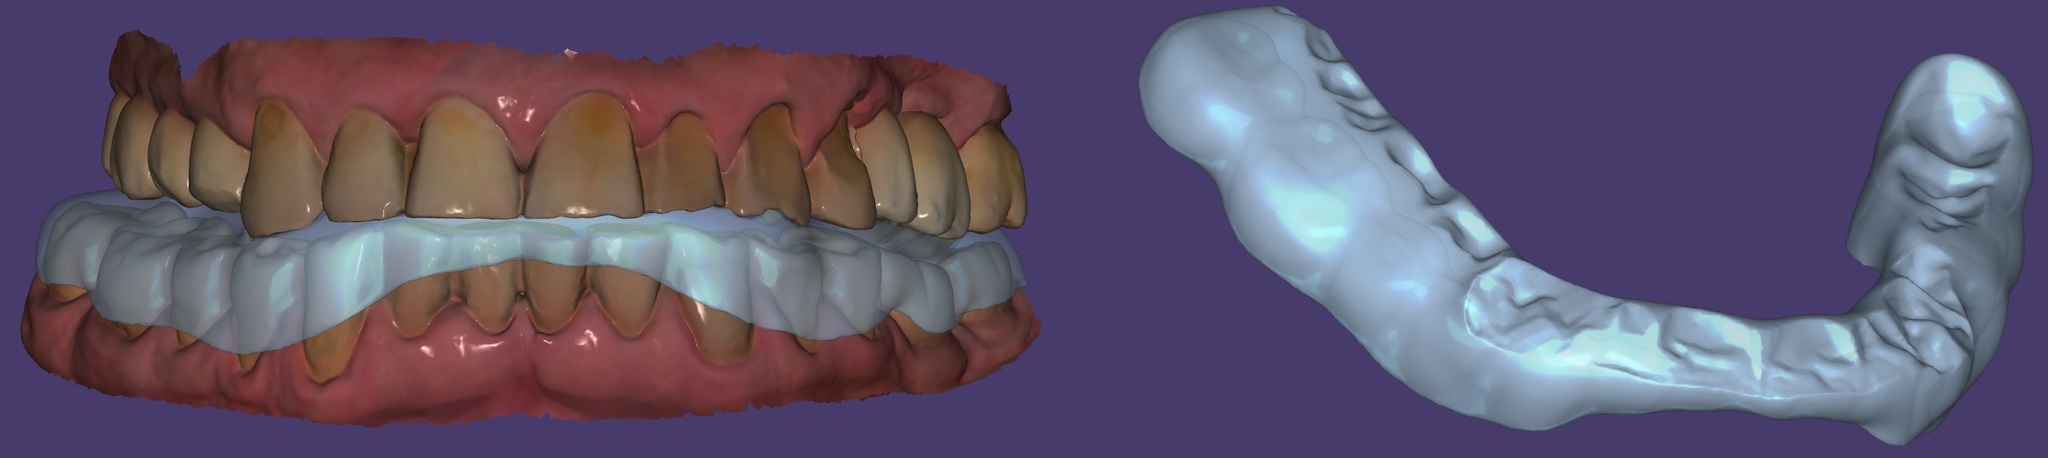

Сканирование челюстей для изготовления ночной капы:

Моделирование капы: